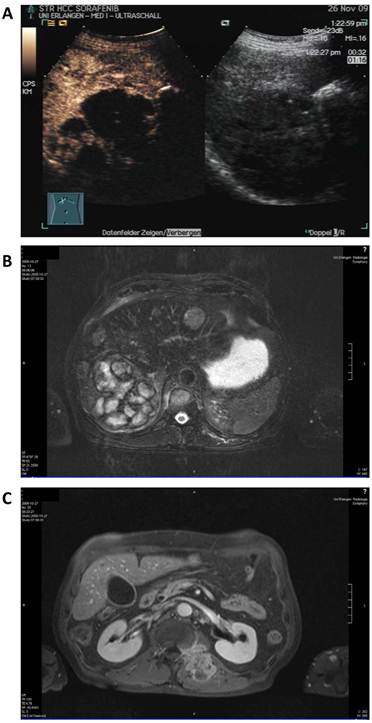

A 68-year old man was diagnosed with advanced multilocular HCC on the basis of ethyltoxic liver cirrhosis (Child-Pugh A) in September 2009. At the time of diagnosis, a moderately differentiated metastasis to the thyroid gland and several metastases to the autochthonic spine musculature and the vertebral bodies with stenoses of the spinal canal (L I) and the neuroforamina (Th XII to L I) were present (Figure 2).

Figure 2

Baseline radiologic assessment of the patient in September 2009 before initiation of sorafenib therapy. A: sonography showing a 10 cm lesion in the liver. B: Magnetic resonance imaging (MRI) of the liver revealing a large lesion in the right liver lobe and several diffuse smaller nodules in the total liver. C: MRI scan of the soft tissue metastasis in the autochthonic spine musculature.